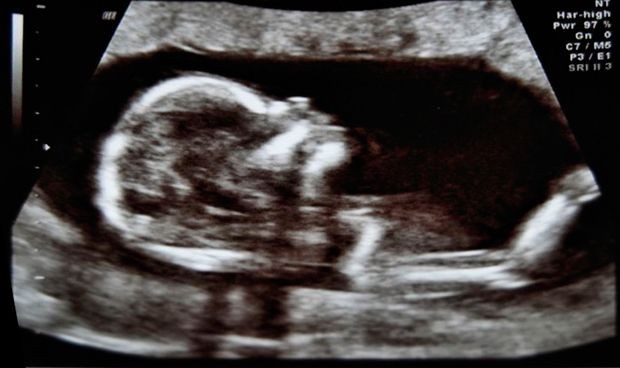

La organización fundamental de las redes cerebrales se establece en el útero durante el segundo y tercer trimestre del desarrollo fetal, según una investigación publicada en JNeurosci, la revista de la Sociedad de Neurociencias de Estados Unidos. Este hallazgo sienta las bases para comprender cómo el período prenatal da forma a la función cerebral futura.

El cerebro funciona como una red compleja de regiones que se comunican entre sí, conocida como el conectoma funcional. Durante el desarrollo fetal, el conectoma funcional comienza a tomar forma ya a finales del segundo trimestre del embarazo.

Los investigadores examinaron a 105 mujeres embarazadas entre las 20 y 40 semanas de gestación que participaron en un estudio de resonancia magnética funcional (fMRI), una tecnología no invasiva que permite a los investigadores observar las conexiones que se forman en el cerebro fetal.

Los investigadores encontraron que los fetos del segundo y tercer trimestre poseen un plan para la conexión funcional. En comparación con el conectoma adulto maduro, el conectoma fetal mostró una superposición del 61 por ciento en las funciones motoras, visuales, auditivas y algunas cognitivas.